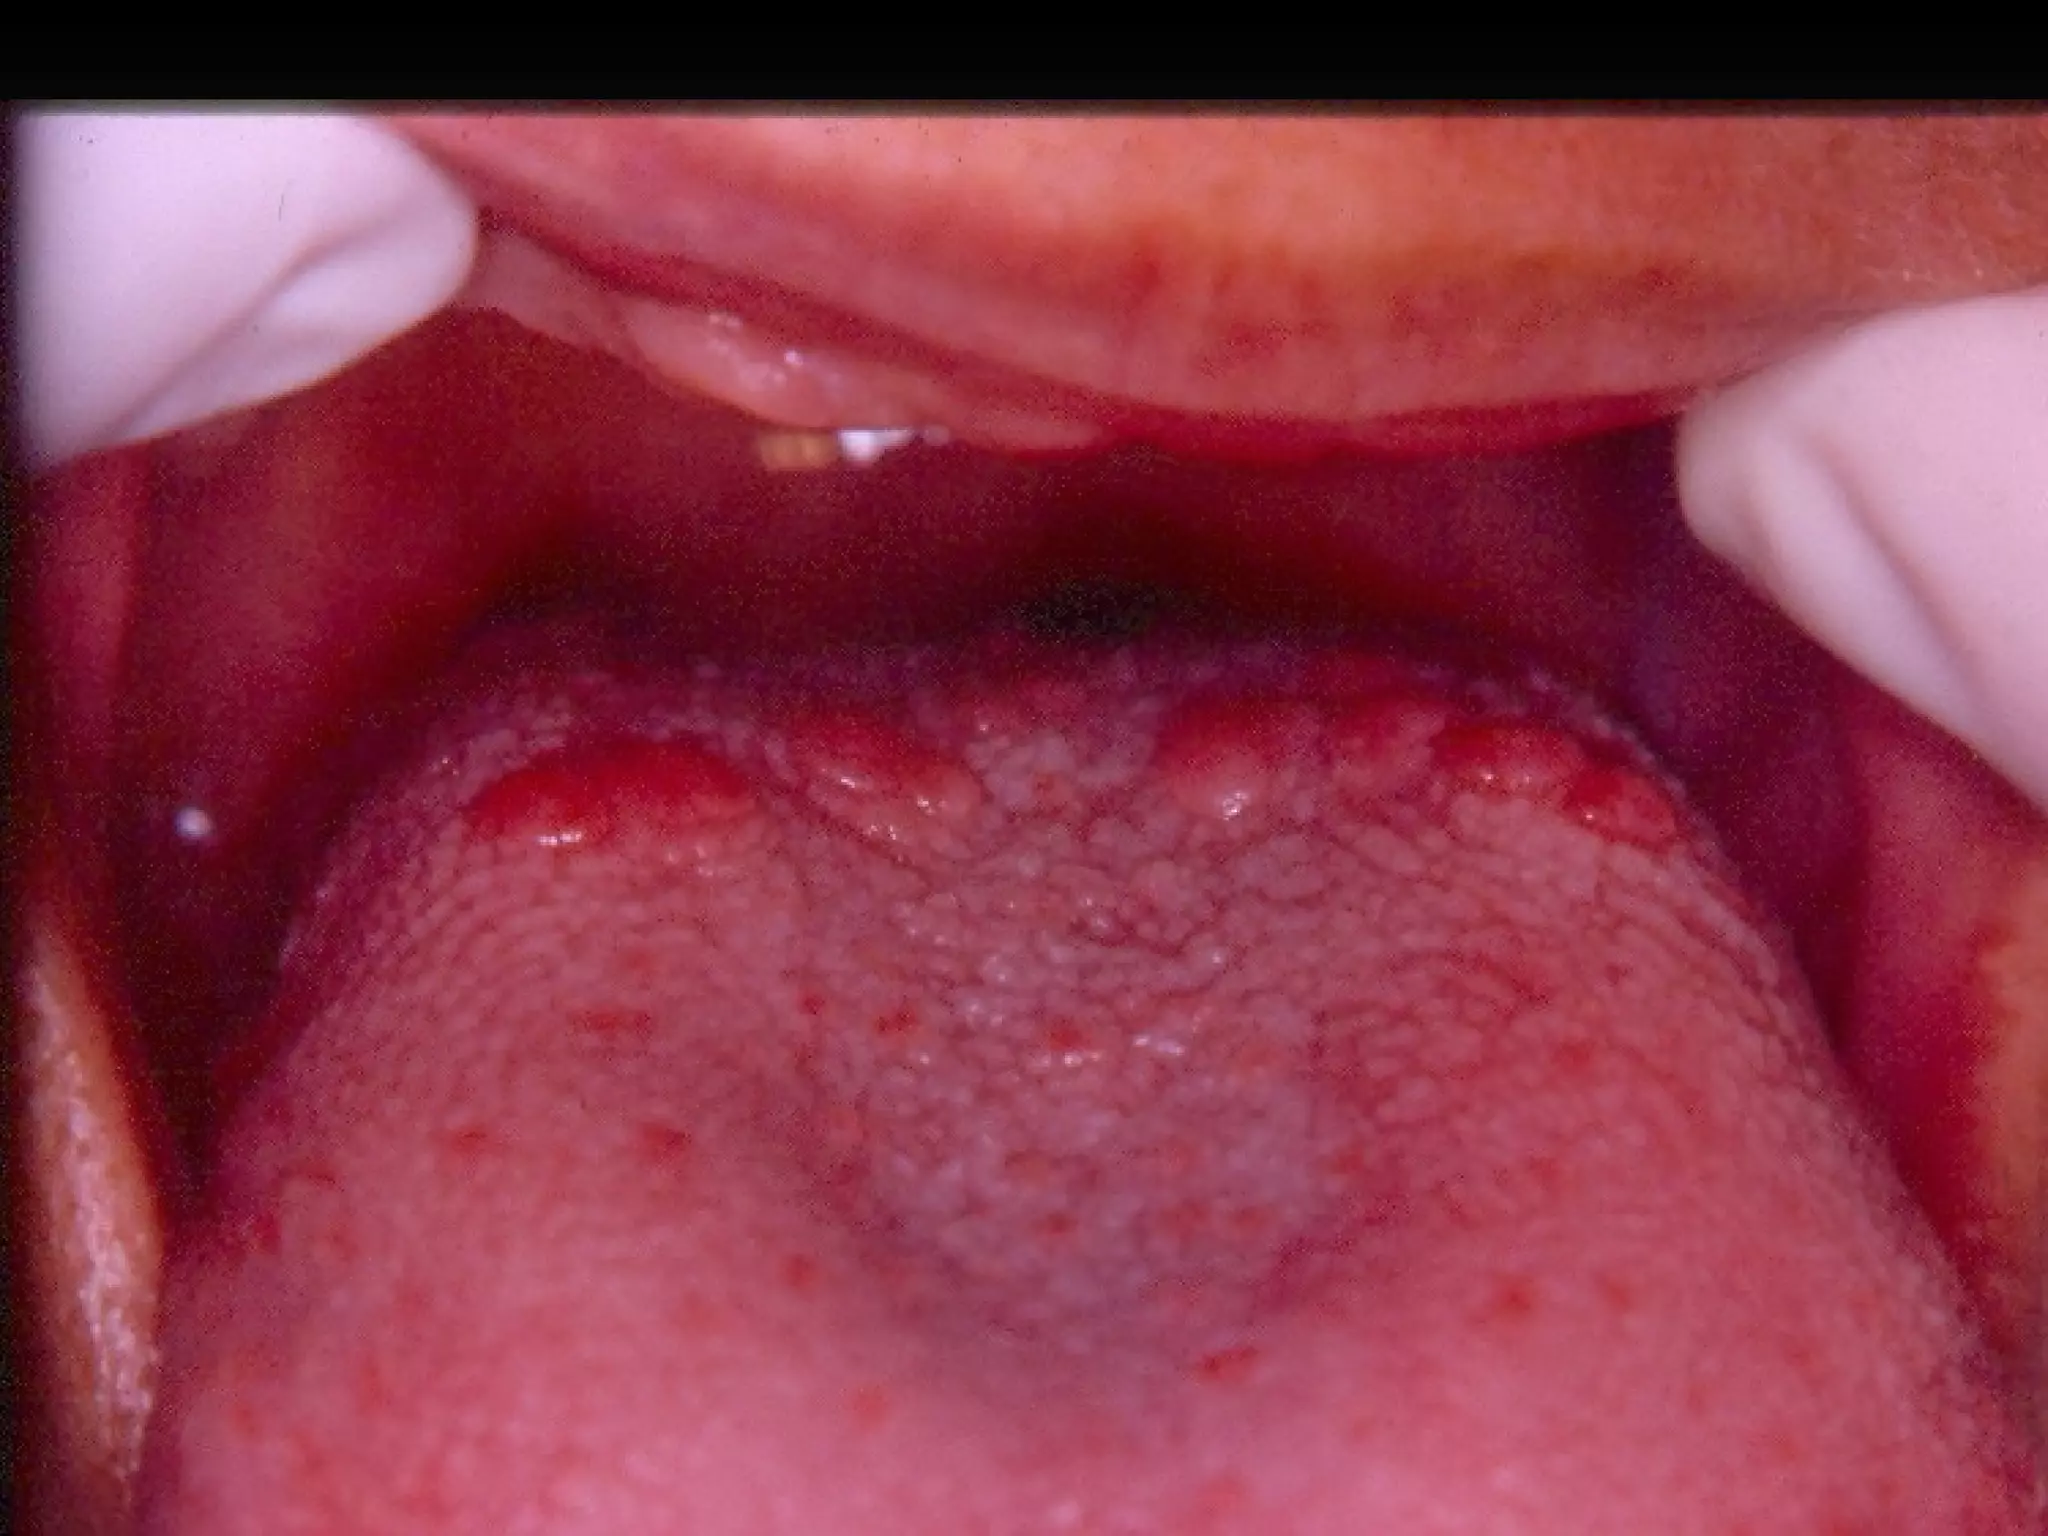

Lesões Fundamentais Lesões com conteúdo líquido Vesícula Bolha Pústula / Hemoflictena

Lesões Fundamentais – Vesícula e Bolha Conteúdo líquido:  vesícula ou bolha